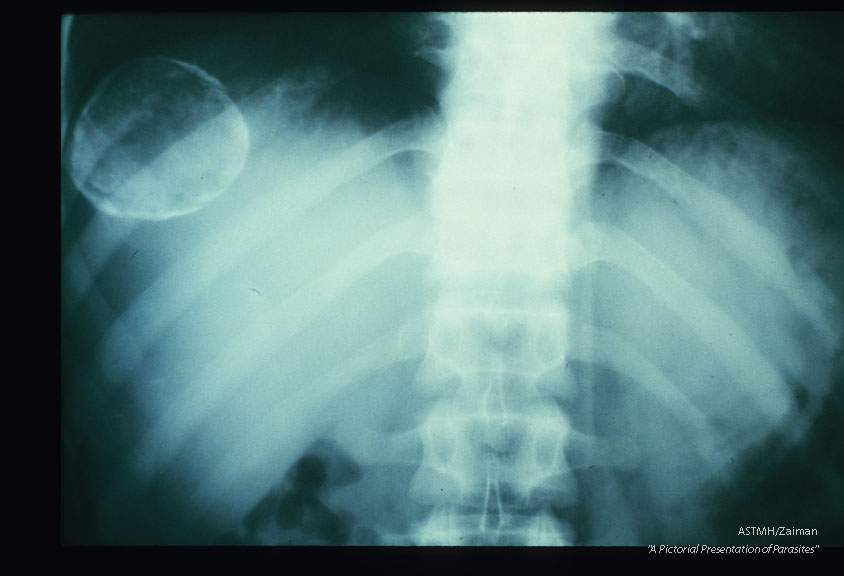

A moderately large calicifed cyst is present in the right upper lobe of the liver. It presents as a white circular line of calcium. Amorphous calcium is projected within the limiting circle. This cyst would be difficult to remove because of its position near the diaphragm.

Echinococcus granulosus